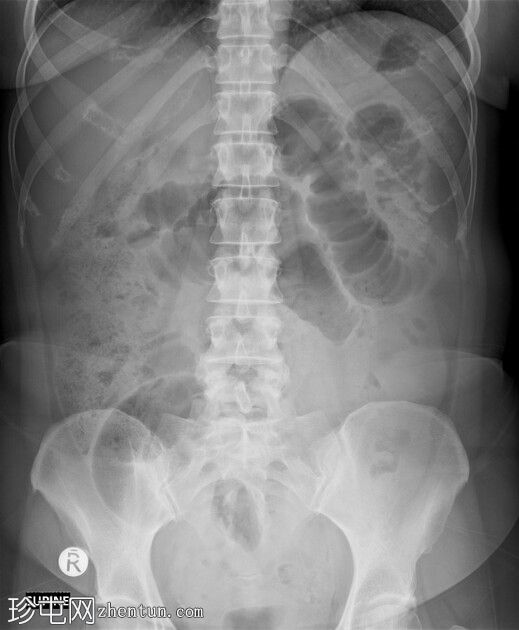

X线片

1.jpeg

正位片

多发扩张的小肠袢,直径最大达4厘米,位于肠腔中央

呈“阶梯状”堆叠外观,肠壁环状皱襞明显,贯穿整个肠腔

结肠内气体稀少

无气腹